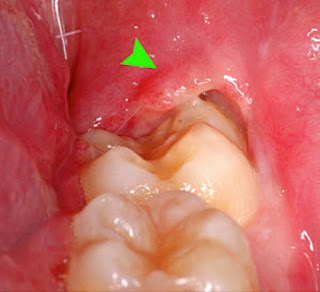

Διακρίνεται σε οξεία και χρόνια.

Στην οξεία φάση έχουμε πόνο, μπορεί να έχουμε κακουχία, πυρετό και πρησμένους λεμφαδένες. Απόστημα μπορεί να δημιουργηθεί, το οποίο μπορεί να επεκταθεί στους παρακείμενους ιστούς, ενισχύοντας τα παραπάνω συμπτώματα.

Συμπληρωματικά μπορεί να υπάρχει δυσοσμία, κακή γεύση, τρισμός (δυσκολία στο άνοιγμα του στόματος), δυσφαγία, δυσκαταποσία (δυσκολία στη μάσηση και την κατάποση) και σα συνέπεια απώλεια της όρεξης.

| Περιστεφανίτιδα |

Στη χρόνια φάση τα συμπτώματα είναι ηπιότερα. Κατά διαστήματα η χρόνια περιστεφανίτιδα μπορεί να μεταπέσει σε οξεία. Κόπωση, άγχος, στρες, ίωση και γενικότερη πτώση των αντιστάσεων του οργανισμού, μπορεί να προκαλέσει παρόξυνση της περιστεφανίτιδας.

Πόνος στην περιοχή μπορεί επίσης να οφείλεται σε τερηδονισμό, πολφίτιδα ή και νέκρωση του φρονιμίτη ή του παρακείμενου δεύτερου γομφίου, το οποίο δεν πρέπει να μας διαφύγει κατά την εξέταση. Επίσης προβλήματα της σύστοιχης κροταφογναθικής διάρθρωσης, ή μία τυπική ωτίτιδα μπορούν να προκαλούν πόνο.